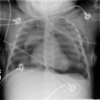

RN a termo.

Cardiomegalia massiva em um neonato com pulmão normal (sem edema alveolar ou intersticial, sem derrame pleural)

Cardiomiopatia neonatal.